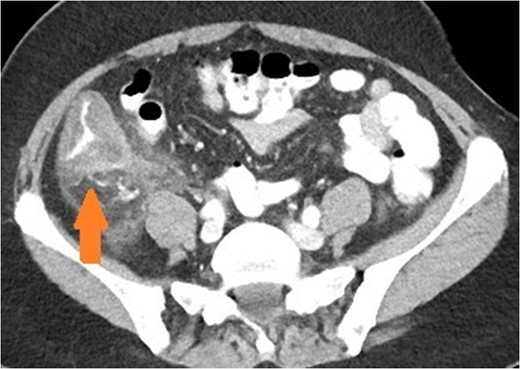

Axial view of patient with appendicitis. Eccentric caecal wall thickening (maximal surrounding the appendiceal orifice) with layered mural contrast enhancement secondary to prominent submucosal oedema (arrow) and prominent pericolic fat stranding represent the CT manifestation of the surgical phlegmon.

Appendicitis features include a fluid-filled dilation (>6 mm) and thickening of the appendiceal wall with mild-to-moderate peri-appendiceal fat stranding [5]. Peri-caecal inflammation may occur, characterised by segmental eccentric bowel wall thickening centred over the appendiceal orifice. Importantly, the submucosa (expanded and low density), muscularis and serosa (both slightly thickened and enhancing more than normal) may be delineated in a stratified or layered pattern. Other complications may be present such as perforation or abscess formation, which are seen as rim enhancing collections. Rarely, hepatic abscesses may be present as a manifestation of portal pyaemia, characterised by diffuse liver lesions close to the portal vein tributaries.